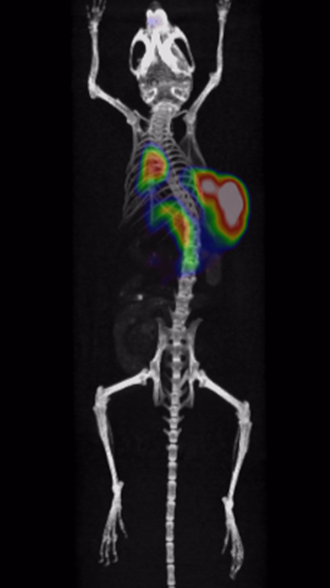

It has been proved that Cu-64-marked nanoantibodies are well-targeting for tumors, with high local uptake and long retention